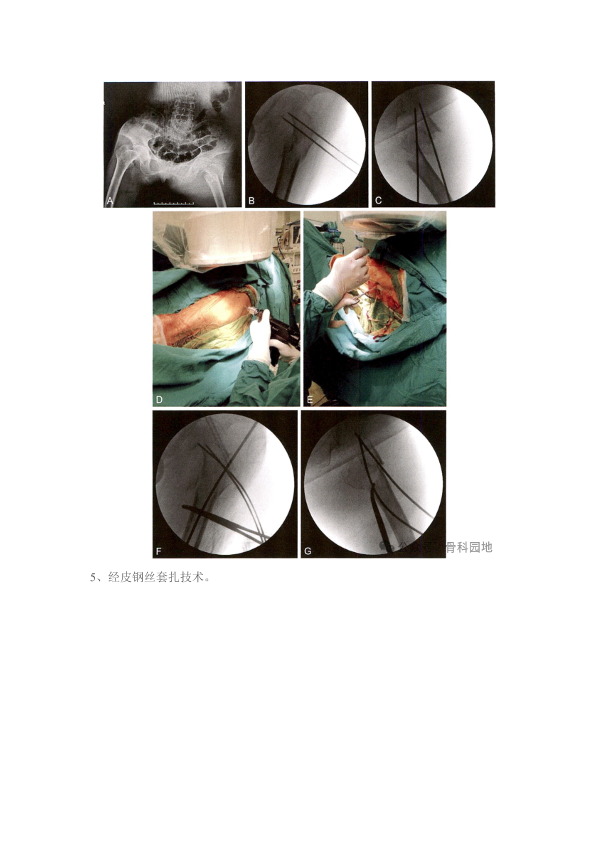

转子下骨折复位难?髓内钉精准复位技巧